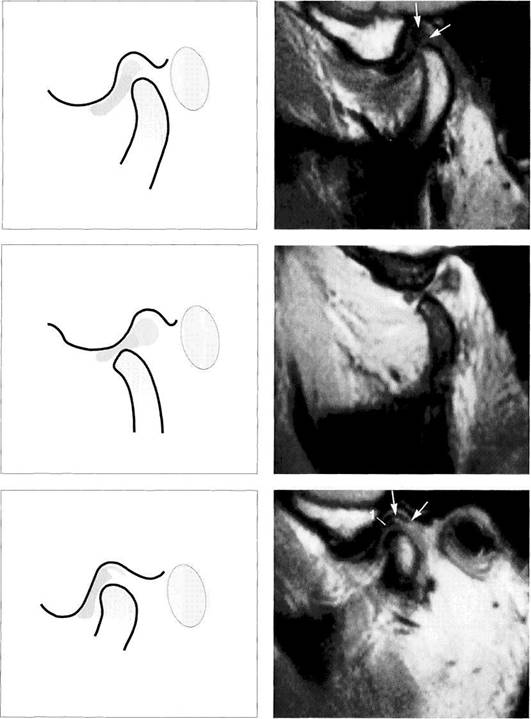

Physiological disk position

Under normal conditions, the pars intermedia (*) of the disk lies be­tween the anterosuperior curva­ture of the condyle and the articular protuberance (arrows). The posi­tion of the posterior border of the pars posterior relative to the vertex of the condyle varies according to the inclination of the protuberance and is therefore not a reliable pa­rameter.

The arrows in this schematic draw­ing mark the relative positions of the condyle and the pars interme­dia to one another.

Insidious disk displacement or a tendency to anterior disk displacement

The pars intermedia lies well in front of the shortest distance be­tween condyle and protuberance (arrows), but the pars posterior (1) still lies on the condyle. Clinically, there are no clicking sounds during jaw opening.

Right: Drawing of a joint with a ten­dency to anterior disk displace­ment. The arrows mark the discrep­ancy between pars intermedia and condyle.

Definite disk displacement

Left: Both the pars intermedia (*) and the posterior border of the pars posterior lie in front of the most anterosuperior curvature of the condyle (arrows). Unless this is a case of disk displacement without repositioning, a clicking sound will occur regularly during jaw opening.

Right: Schematic drawing of a defi­nite anterior disk displacement. The arrows mark the discrepancy between the pars intermedia and condyle.

Disk position in the frontal plane

Left: Schematic drawing illustrating normal disk position in the frontal plane.

Right: MRI of the right temporo­mandibular joint of a 24-year-old man. The frontal plane is angled so that it is parallel with the long axis of the condyle. With the jaws closed, the pars posterior of the disk is centered over the condyle.

Medial disk displacement

Left: Schematic drawing of a medial disk displacement in the frontal plane.

Right: MRI of the right temporo­mandibular joint of a 24-year-old patient. An adequate diagnosis of lateral and medial disk displace­ments cannot be made with arthrography and arthrotomogra-phy alone (Kurita et al. 1992a,b).

Lateral disk displacement

Left: Schematic drawing of a lateral disk displacement in the frontal plane.

Right: MRI of the right temporo­mandibular joint of a 23-year-old woman who sustained a fracture of the neck of the condyle at age 14 years. The condyle was tipped medially and has healed in an ab­normal position. The lateral disk displacement is causing pain and recurring limitation of jaw opening.